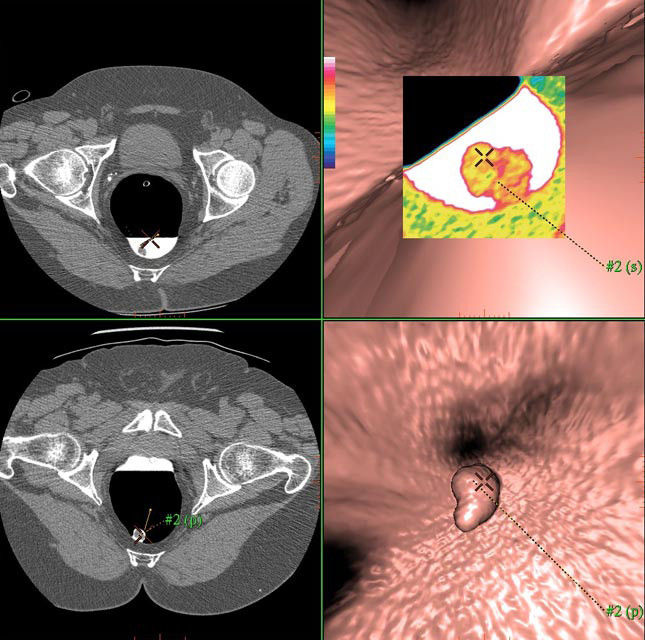

Colon VCAR gives you an efficient reading workflow solution for detecting colonic lesions. The program allows you to read and problem solve in 2D, 3D, or 360 degree dissection views. With it you can visualize anatomy that would otherwise be obscured by tagged fluid. Also, the program lets you generate a clear, concise clinical report specifically designed to communicate vital medical information to referring clinicians and patients.

• Virtual biopsy tool aids problem solving in 3D views with color-coded or black/white scales.